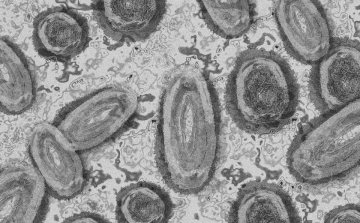

Még több hónapon át folytatódik a majomhimlő elleni oltási kampány Franciaországban

Franciaországban még több hónapon át folytatódik a majomhimlő elleni oltási kampány 2022-ben és várhatóan 2023 elején is, miután az általános megelőzés következtében most először csökkeni kezdtek a mutatók